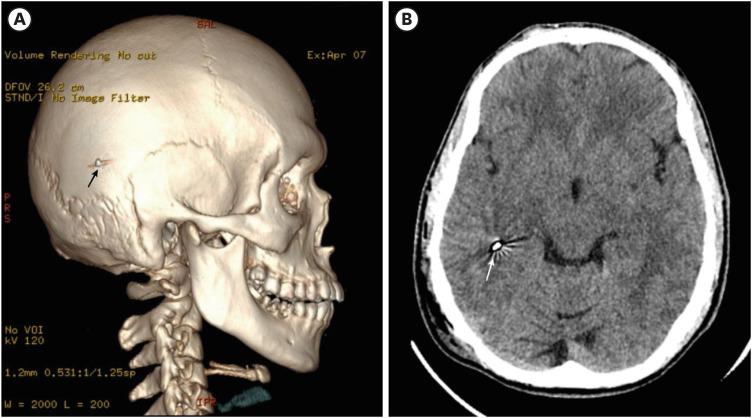

This study presents a case of penetrating craniocerebral injury resulting from a nail gun accident, which is a rare etiology for penetrating brain injuries. Immediate surgical intervention is crucial to mitigate the risk of infection. The patient was a 28-year-old male who underwent craniotomy for foreign body extraction and debridement following presentation. Preoperative imaging aided in the precise localization of the injury, and guided the surgical approach. The surgical technique focused on minimizing brain tissue manipulation to prevent further damage. Postoperative care included prophylactic antibiotics and antiseizure medications. No neurological deficits or signs of infection were found on follow-up examination. Nail gun-related injuries are rare; in this case, prompt surgical intervention and meticulous postoperative care contributed to favorable outcomes, emphasizing the importance of timely management in such cases.

本研究报告了一例因射钉枪意外导致的穿透性颅脑损伤病例,这是穿透性脑损伤的一种罕见病因。立即进行手术干预对于降低感染风险至关重要。患者为一名28岁男性,就诊后接受了开颅异物取出和清创手术。术前影像学检查有助于精确确定损伤部位,并指导手术入路。手术技术的重点是尽量减少对脑组织的操作,以防止进一步损伤。术后护理包括预防性使用抗生素和抗癫痫药物。随访检查未发现神经功能缺损或感染迹象。与射钉枪相关的损伤很少见;在本病例中,及时的手术干预和精心的术后护理促成了良好的结果,强调了在此类病例中及时处理的重要性。